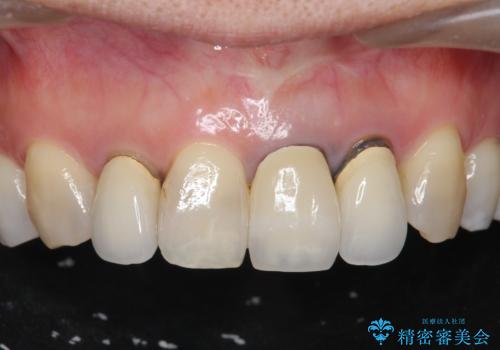

前歯のフチが黒いのが気になる 前歯のセラミック治療

- 前歯のクラウンの歯肉の位置が年々変化し、歯ぐきのフチが黒くなってしまった、綺麗にしたいと希望されて来院されました。

周囲の歯に調和したセラミッククラウンを作製し、審美性を大幅に向上させることができました。